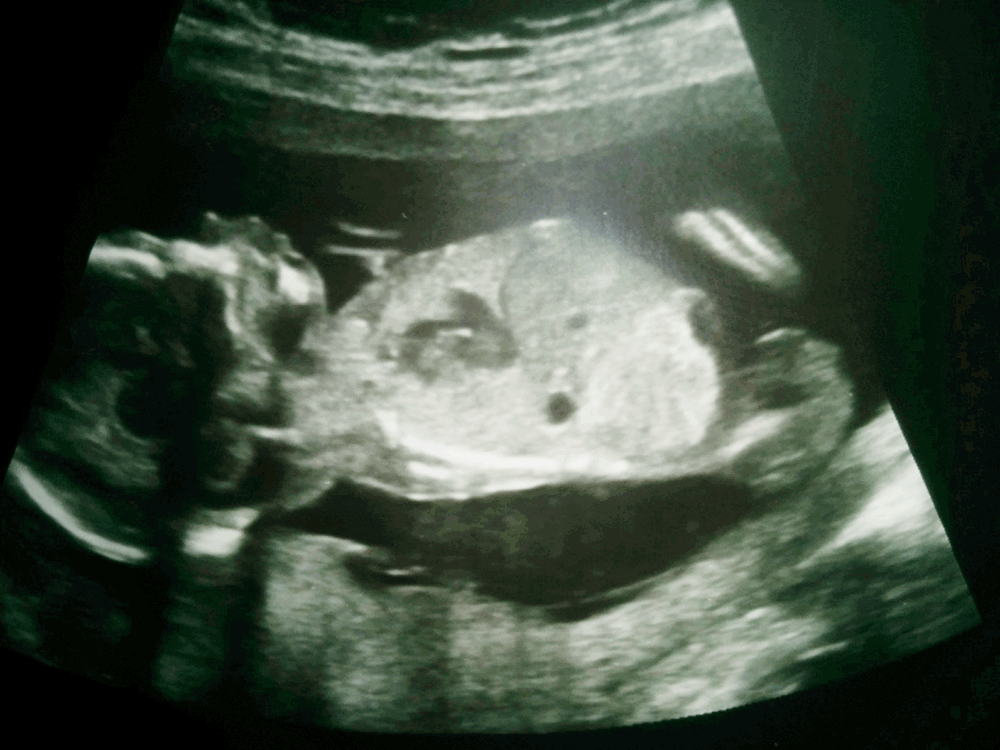

Hi all, do you have any guesses from this pic? Thanks! Attachment 35842